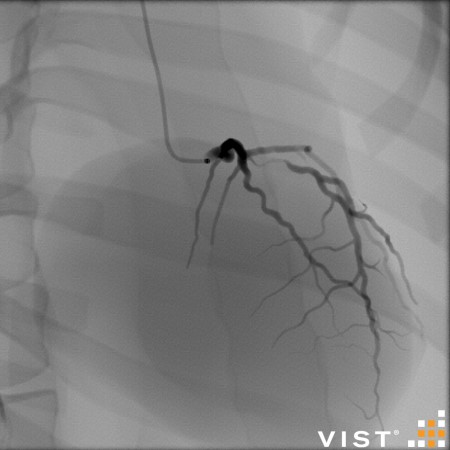

Simuladores Endovanculares.

módulos内血管分发

Aquíhayuna listademódulosundonibles concatibles con el simulador vist g5(Versiónforporidenteyy lab,没有兼容的孔血管y vist灯)。Esta listaestántancoreeevolución,没有Dude en advertarla promicy ... los dutallesestándisponibles haciendo clic en eltítulodelmódulo(网站蒙黛尔,enInglés)